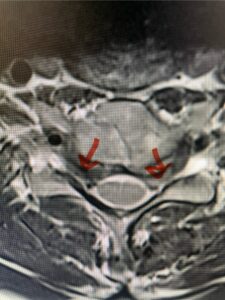

This 61-year-old female with a history of severe osteoporosis and a prior history of a laminectomy from l2-S1 with an L5-S1 instrumented fusion, presents with progressive low back pain and right lower extremity radiculopathy. MRI revealed a grade 1 L2-3 spondylolisthesis with severe stenosis mainly from severe right L2-3 facet joint hypertrophy which was compressing the right L3 descending nerve root. (Fig. 1). She had failed conservative management consisting of physical therapy and pain management with epidurals. She underwent an L1-3 revision laminectomy where we had to dissect a plane underneath the inferior aspect of the L2 lamina. We performed an instrumented fusion at L2-3 with special hydroxyapatite-coated screws to improve fixation to surrounding bone given here severe osteoporosis (Fig. 2) This worked out well and the patient had an uneventful recovery with relief of her leg pain.

Figures 1a: Sagittal and axial T2-weighted lumbar MRIs demonstrating a grade 1 L2-3 spondylolisthesis (red arrow) with severe stenosis secondary to right L2-3 facet hypertrophy (red arrow).

Fig 1b: Note the left L2-3 facet joint (blue arrow) is normal in size compared to the right (red arrow)